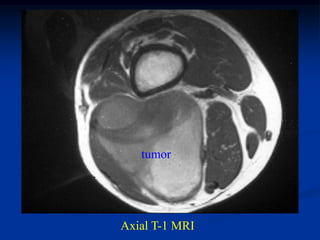

CLASSIC

Case #270

72 year male with an

intramuscular lipoma

quadriceps muscle

Coronal T-1 MRI

Another coronal T-1 MRI

Axial T-1 MRI